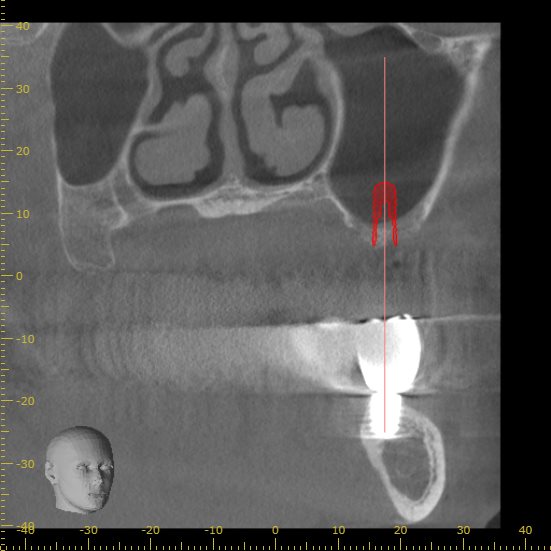

正面から見た画像です。

インプラントの半分以上に骨が足りない状態です。

現状の骨の状態でインプラントを行うこと自体が難しいと判断できます。

実際の処置後です。

下の歯と本数を揃えるため、計画を再立案し3本のインプラントを埋入しました。

インプラントの上にドーム状に広がっているのがサイナスリフトを行い填入された人工骨です。

予定通りの場所に、予定通りの方法でインプラント手術を終えることができました。